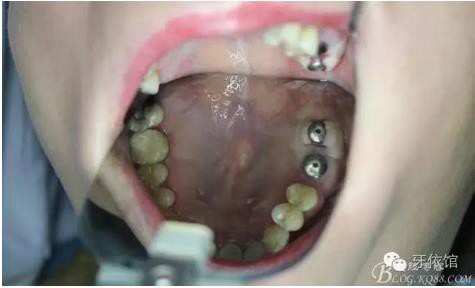

三周后右上6,7

戴入后口內(nèi)照